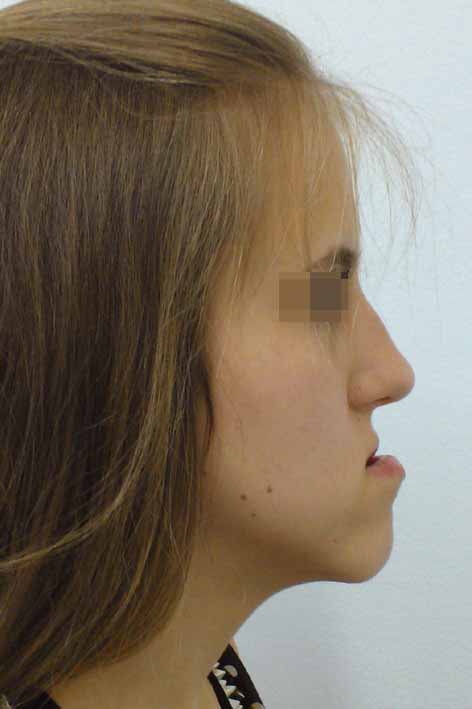

Лицева корекция преди и след лечението – случай на доц. Джоров

В процеса на стареене се задълбочават челните бразди, западат веждите, отпускат се клепачите, загубва се окръглената форма на бузите и се появяват хлътнали линии по шията. Операциите, за корекция на тези процеси, са блефаропластика (корекция на клепачите), повдигане на челото и веждите (фейс-лифт), септоринопластика (корекция на носа и носната преграда), отопластика (корекция на ушите), ментопластика (корекция на брадата) и др.

Корекция на брадата преди и след лечението – случай на доц. Джоров